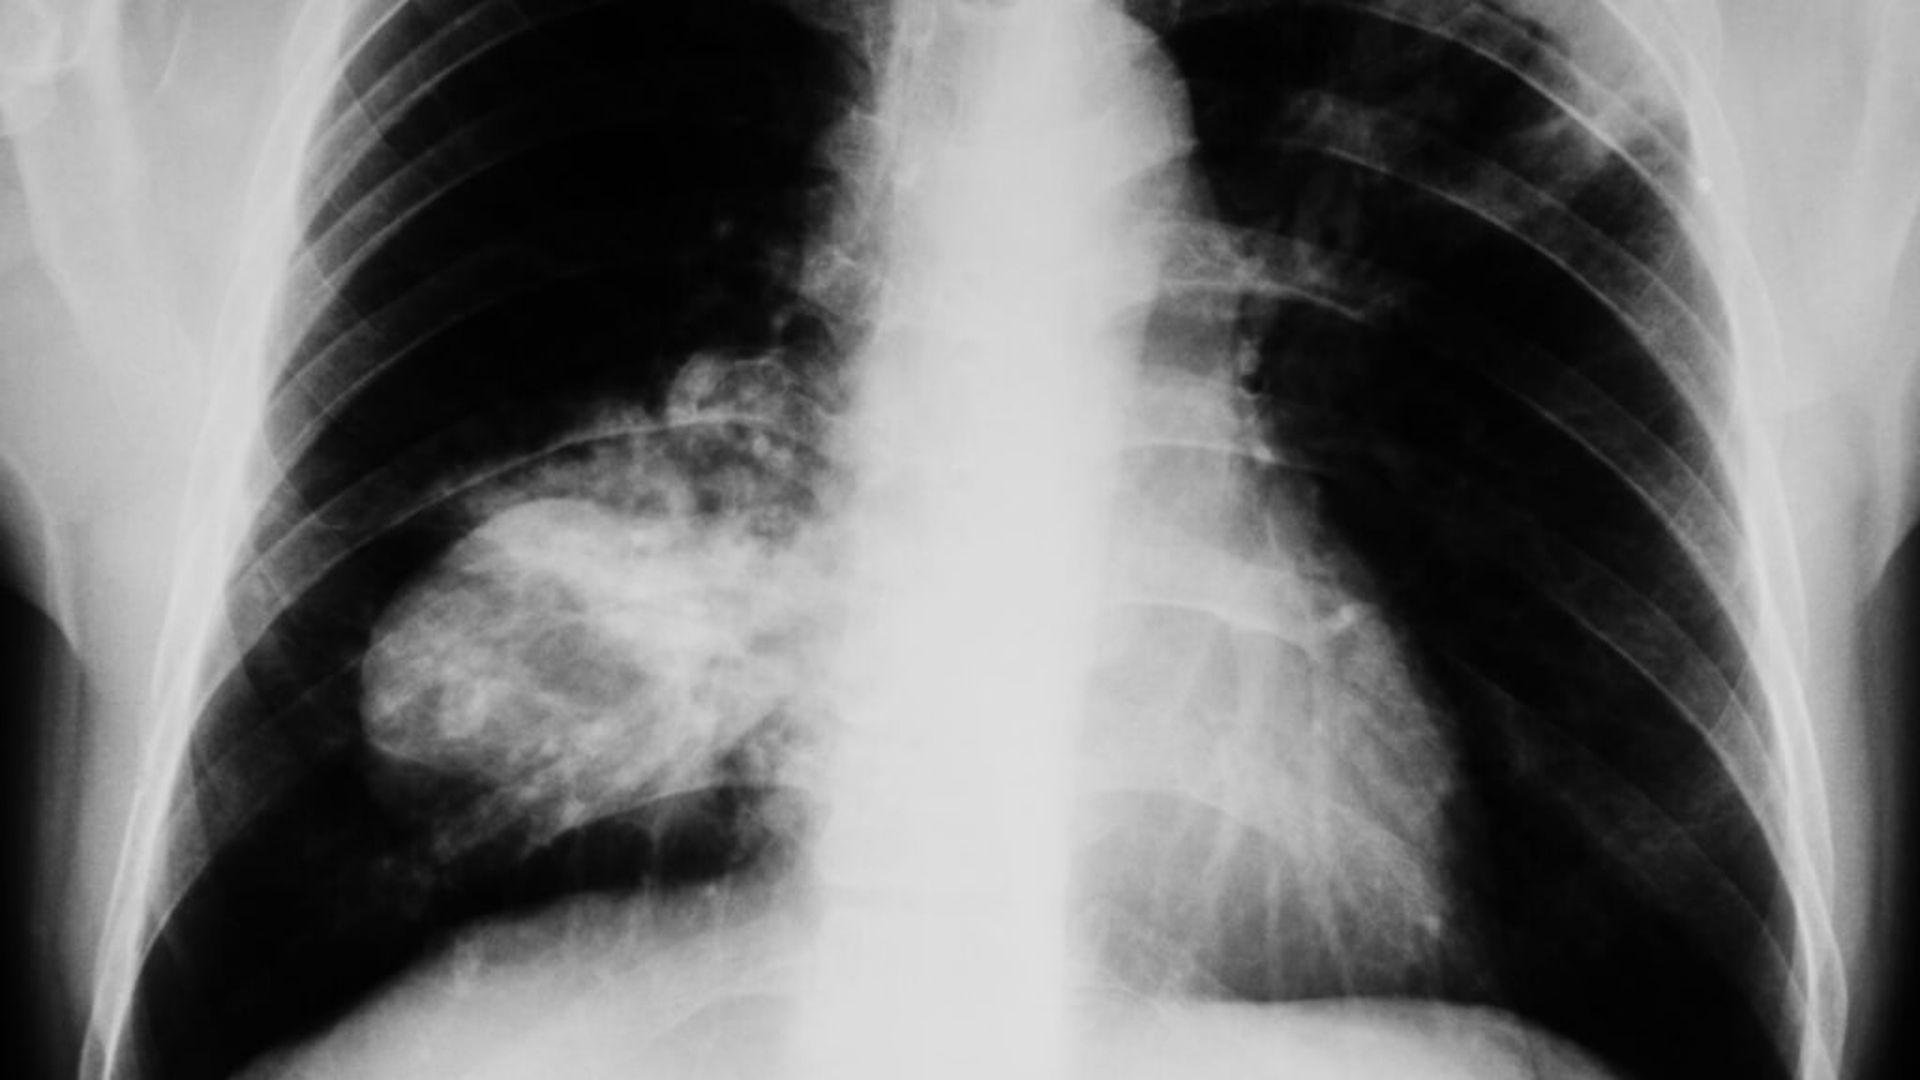

El cáncer de pulmón es la tercera causa de muerte en España, en 2023 causó más de 22.700 fallecimientos, con un incremento del 4,2% en la mortalidad femenina. Son varios los procedimientos que existen para tratar esta enfermedad, sin embargo, no todos los pacientes responden de igual forma a cada uno de estos. Por ello, investigadores de la Escuela Técnica Superior de Ingeniería Informática de la Universidad de Sevilla, del Hospital Virgen del Rocío y del Virgen Macarena han desarrollado una innovadora investigación que utiliza inteligencia artificial para predecir los efectos secundarios de los tratamientos que se utilizan en pacientes de cáncer de pulmón. El estudio, publicado en la prestigiosa revista 'Clinical and Translational Radiation Oncology', supone un destacado avance en la personalización de los tratamientos oncológicos, pues ayudará a predecir complicaciones y facilitará a los oncólogos la toma de decisiones para minimizar los riesgos asociados a los tratamientos, ha informado este martes en un comunicado la Universidad de Sevilla.

El estudio en cuestión se basa en un análisis exhaustivo de datos reales de 875 pacientes con cáncer de pulmón, empleando modelos de Inteligencia artificial, para predecir seis tipos de efectos secundarios a la radioterapia, como la esofagitis aguda o la disnea crónica. Según José Luis López Guerra, jefe de la UGC de Oncología Radioterápica del Virgen del Rocío, “este trabajo supone un importante avance en el conocimiento detallado de los efectos secundarios asociados a la radioterapia en pacientes con cáncer de pulmón. Nos permitirá predecir con antelación qué pacientes tienen mayor riesgo de padecer complicaciones, lo que facilita la toma de decisiones en cuanto a los tratamientos y la adopción de medidas preventivas para evitar estos efectos”. El trabajo, publicado en la prestigiosa revista Clinical and Translational Radiation Oncology, ha sido desarrollado en la Unidad de Gestión Clínica (UGC) de Oncología Radioterápica del Hospital Universitario Virgen del Rocío, en colaboración con la Unidad de Innovación y Análisis de Datos del Hospital Universitario Virgen Macarena y el Departamento de Lenguajes y Sistemas Informáticos de la Universidad de Sevilla. La investigación, que ha sido presentada como tesis doctoral en la Escuela Técnica Superior de Ingeniería Informática de la Universidad de Sevilla, destaca como un avance significativo en el campo de la oncología radioterápica y abre nuevas vías para la personalización de los tratamientos y la mejora de la calidad de vida de los pacientes. Aunque la investigación se publicó en 2023, acaba de recibir el Premio de la Cátedra Universitat de Barcelona-Atrys de Radioterapia Personalizada, que ha sido entregado a Kiko Núñez, investigador de la Universidad Hispalense que lidera el estudio, durante el XXII Congreso de la Asociación Española de Oncología Radioterápica (SEOR) celebrado en Oviedo.